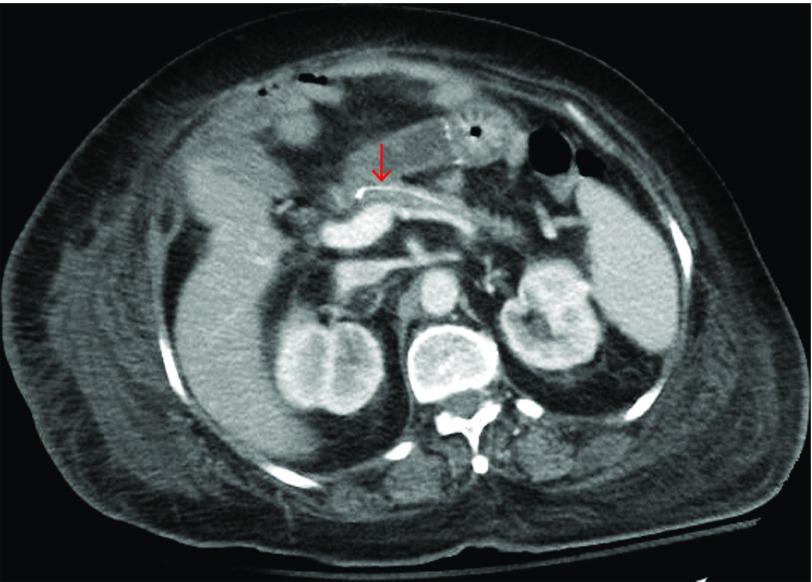

Pancreaticoduodenectomy, or Whipple procedure, is a high-risk surgical procedure commonly performed for tumors of the pancreatic head. The pancreatico-enteric anastomosis is an important component of this procedure. The maturation and adequate healing of this anastomotic site is critical to decrease the risk of postoperative pancreatic fistulas. The use of stents can help in the healing of this anastomotic site. We present a patient with pancreatic adenocarcinoma who underwent pancreaticoduodenectomy, and presented with progressively worsening lumbar pain 7 years later. The patient was found to have osteomyelitis as a complication from an entero-spinal fistula secondary to a migrated pediatric feeding tube that was placed at the pancreaticojejunal anastomosis.

胰十二指肠切除术,即惠普尔手术,是一种常用于治疗胰头肿瘤的高风险外科手术。胰肠吻合术是该手术的重要组成部分。此吻合口部位的成熟和充分愈合对于降低术后胰瘘风险至关重要。使用支架有助于该吻合口部位的愈合。我们报告一例患有胰腺腺癌的患者,其接受了胰十二指肠切除术,7年后出现进行性加重的腰痛。该患者被发现患有骨髓炎,这是由于放置在胰空肠吻合口处的儿童喂养管移位继发肠-脊柱瘘引起的并发症。